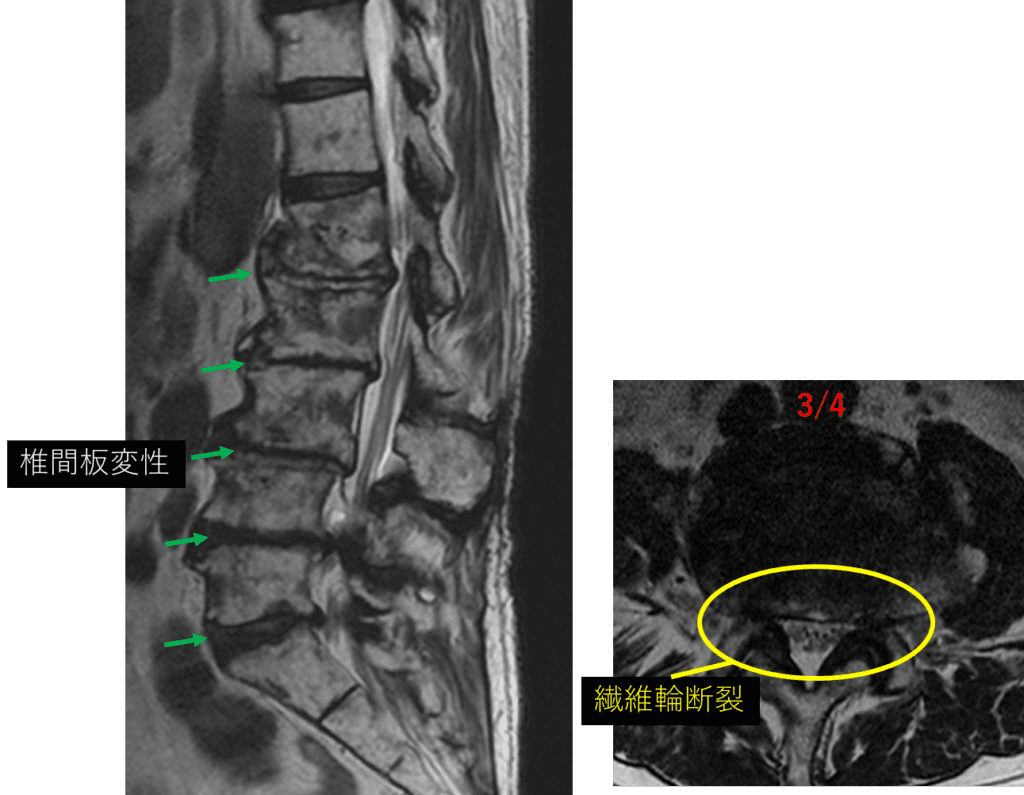

画像及び所見について

L1/2: 椎間板変性、減高

L2/3: 椎間板変性、減高

L3/4: 椎間板変性、減高、繊維輪断裂

L4/5: 椎間板変性、膨隆、右椎間孔狭窄

L5/S: 椎間板変性、膨隆

以上の事が画像上認められます。

L3/4、4/5、5/S に

椎間板変性、減高、膨隆、繊維輪断裂、椎間孔狭窄 を認め、主症状の原因の可能性が高い。